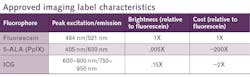

At the moment, only three fluorescent agents see common use for FGS, indocyanine green (ICG), 5-aminolevulinic acid hydrochloride (5-ALA), and fluorescein sodium (see table).1-3 ICG and fluorescein are vascular imaging labels, so they accumulate in places with excess blood flow, which is characteristic of growing tumors. At least in the brain, ICG appears to remain accumulated in tumors about 24 hours after administration, during the so-called second-window. 5-ALA is not a fluorophore, but an intermediate compound in the heme synthesis pathway. Tumors, with their elevated metabolism, are primed to overproduce heme through another chemical intermediate, polyporphyrin-IX (PpIX). With excess 5-ALA provided, these cells produce more PpIX, which fluoresces pink.The factors that influence contrast may vary from cell to cell and tumor to tumor. However, even with that limitation, FGS has already demonstrated its value on some of the toughest tumor targets of all.